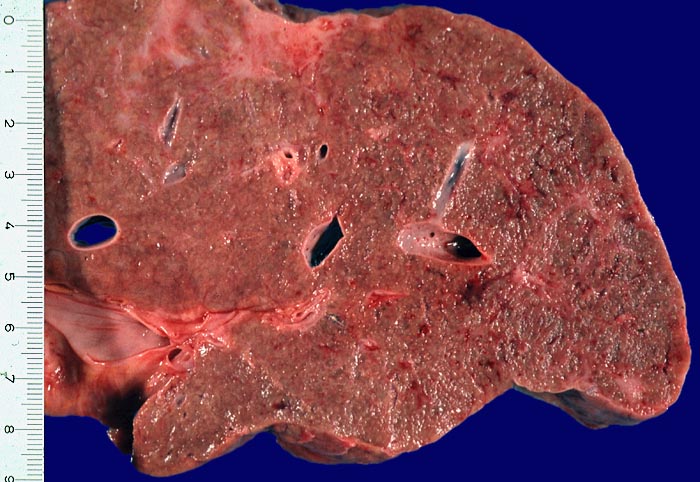

Makroskopie

Befund

Pathologischer Befund

Die meisten chronischen Infektionen mit dem Hepatitis C Virus führen zu einer Hepatitis mit begleitender Fibrose. Für die Gradierung der portalen und intralobulären Entzündungsaktivität und das Staging der Fibrose sind in verschiedenen Kliniken unterschiedliche Klassifikationen gebräuchlich. In der Schweiz wird bevorzugt die Metavir Einteilung verwendet.

• Dichte mononukleäre portale und lobuläre Entzündungsinfiltrate mit Ausbildung von Lymphfollikeln in den Portalfeldern.

• Übergreifen der Entzündung auf das Parenchym (=Interface oder Grenzzonenhepatitis).

• Abgerundete hypereosinophile apoptotische Hepatozyten (Councilman-Körperchen).

• Geringe Portalfeldfibrose. Das sollte der Kliniker dem Pathologen mitteilen: